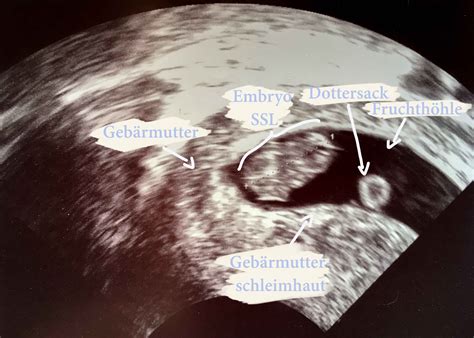

Bei einer Ultraschalluntersuchung in der Frühschwangerschaft zeigt sich eine leere Fruchtblase ohne Dottersack und Embryo. Die Größe der Gebärmutter ist oft kleiner als für die errechnete Schwangerschaftswoche zu erwarten wäre.

Die Diagnose eines Windeis wird in der Regel gestellt, wenn bei einer Ultraschalluntersuchung eine Fruchtblase von mehr als 2 cm Größe festgestellt wird, die von Trophoblasten umgeben ist, aber keinen sichtbaren Embryo im Inneren aufweist. Bei Unsicherheiten bezüglich des Datums der letzten Regelblutung wird empfohlen, die Untersuchung nach 7-10 Tagen zu wiederholen, um eine voreilige Diagnose zu vermeiden. Studien zeigen, dass sich auch bei einer Fruchtblasengröße von über 20 mm noch Embryonen zeigen können. Eine sichere Diagnose wird oft erst ab einer Fruchtblasengröße von mehr als 25 mm oder bei ausbleibendem Wachstum und fehlender Embryonalanlage nach einer Woche gestellt.